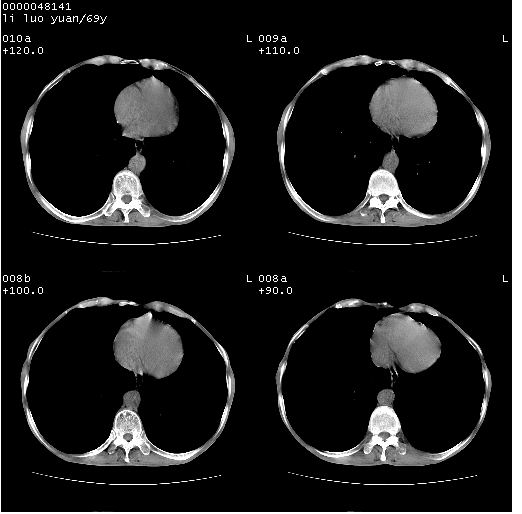

临床资料:老年患者,咯血、消瘦

影像表现:桶状胸,双肺纹理纤细、紊乱,透过度增高,肺野内可见多发、散在、大小不等的无壁高透过影,右肺中叶外侧段分叶样软组织占位,左上肺纤维索条样密度影,相应层面左侧胸腔轻度萎陷,纵隔左移。

影像诊断:1、慢支、肺气肿、双下肺野肺大泡形成

2、左上肺陈旧性肺结核

3、右肺中叶外侧段占位 考虑肺ca可能性较大、建议增强及痰检脱落细胞